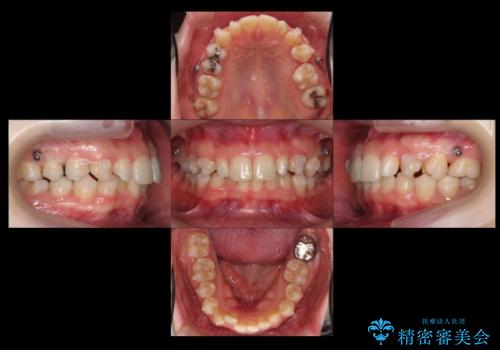

- 前歯を整えたいと来院。

左右の前から2番目の歯が細く、矮小でした。

また、奥歯が2つ並んでおり歯ブラシがしにくい状態でした。

内側に入っている左上5を抜歯しています。

抜歯したスペースを使い、歯並びを整え、さらにその隙間を利用して細い歯を大きく整えてセラミックで被せるという総合的な治療を行いました。

マウスピース矯正→上顎両側2番のセラミック、左下67の虫歯治療 の順で行いました。